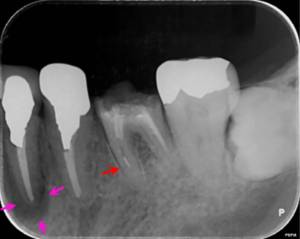

左下6番の歯の根の中に折れている器具(矢印赤)があり、前医ではこれ以上根管治療が不能とのことでした。また、病変のある左下4番の歯の根管治療も提案し、患者様の合意を頂き治療をすすめることになりました。

左図のレントゲン写真では左下4番の歯の根の先に炎症があり骨が溶けている部分があります(矢印ピンク) 。